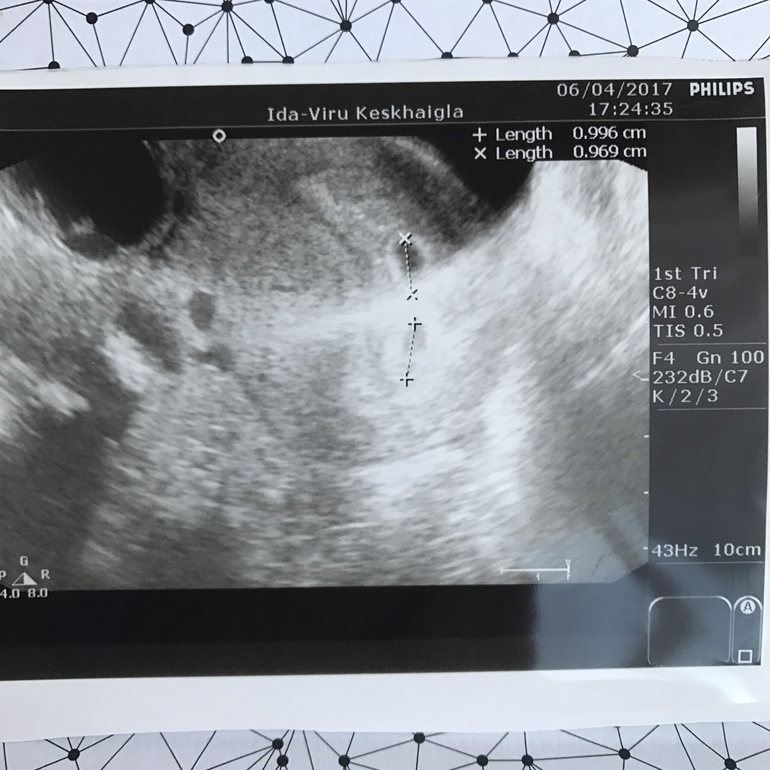

А вот сегодня была на УЗИ получается 21 дпп и у нас два малыша:))))

И фото с УЗИ